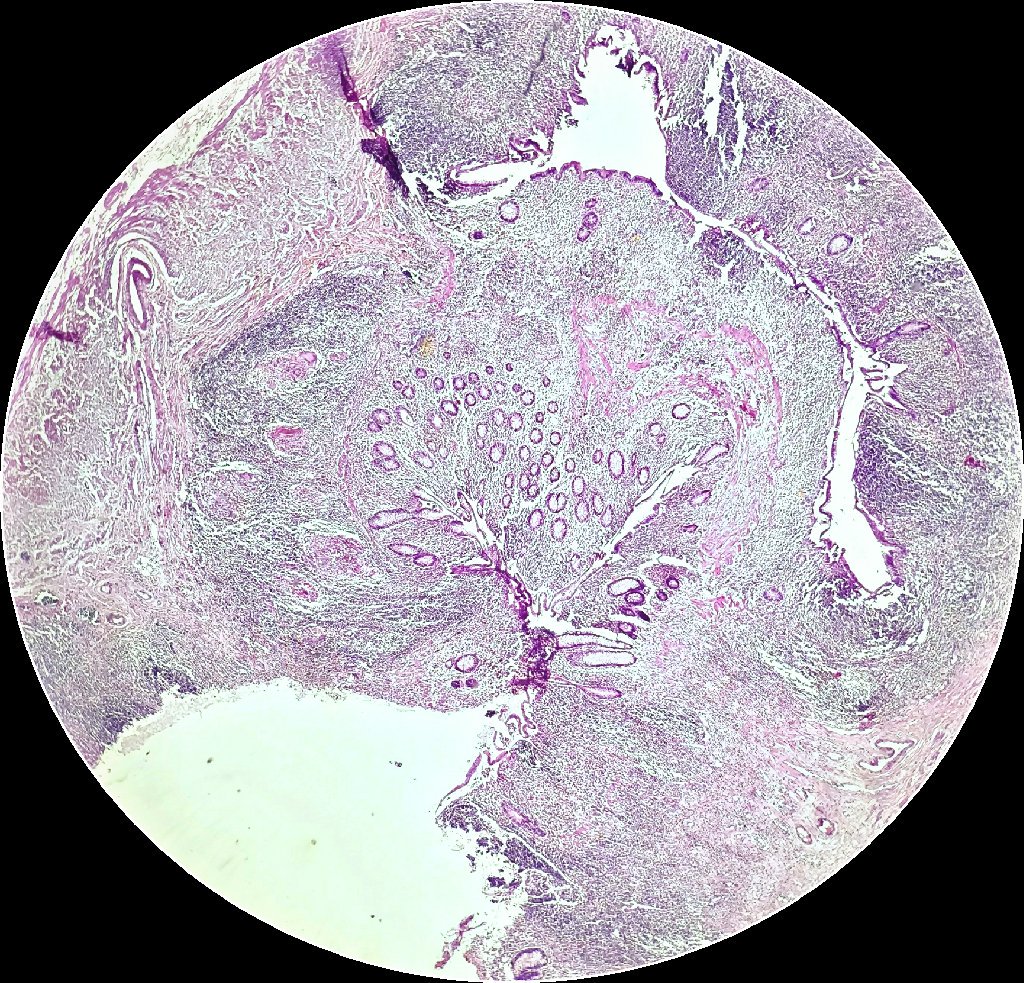

Seminoma with florid granulomatous reaction including necrosis and granulomatous vasculitis.

#GUPath#granuloma pic.twitter.com/AHMrgPUELP